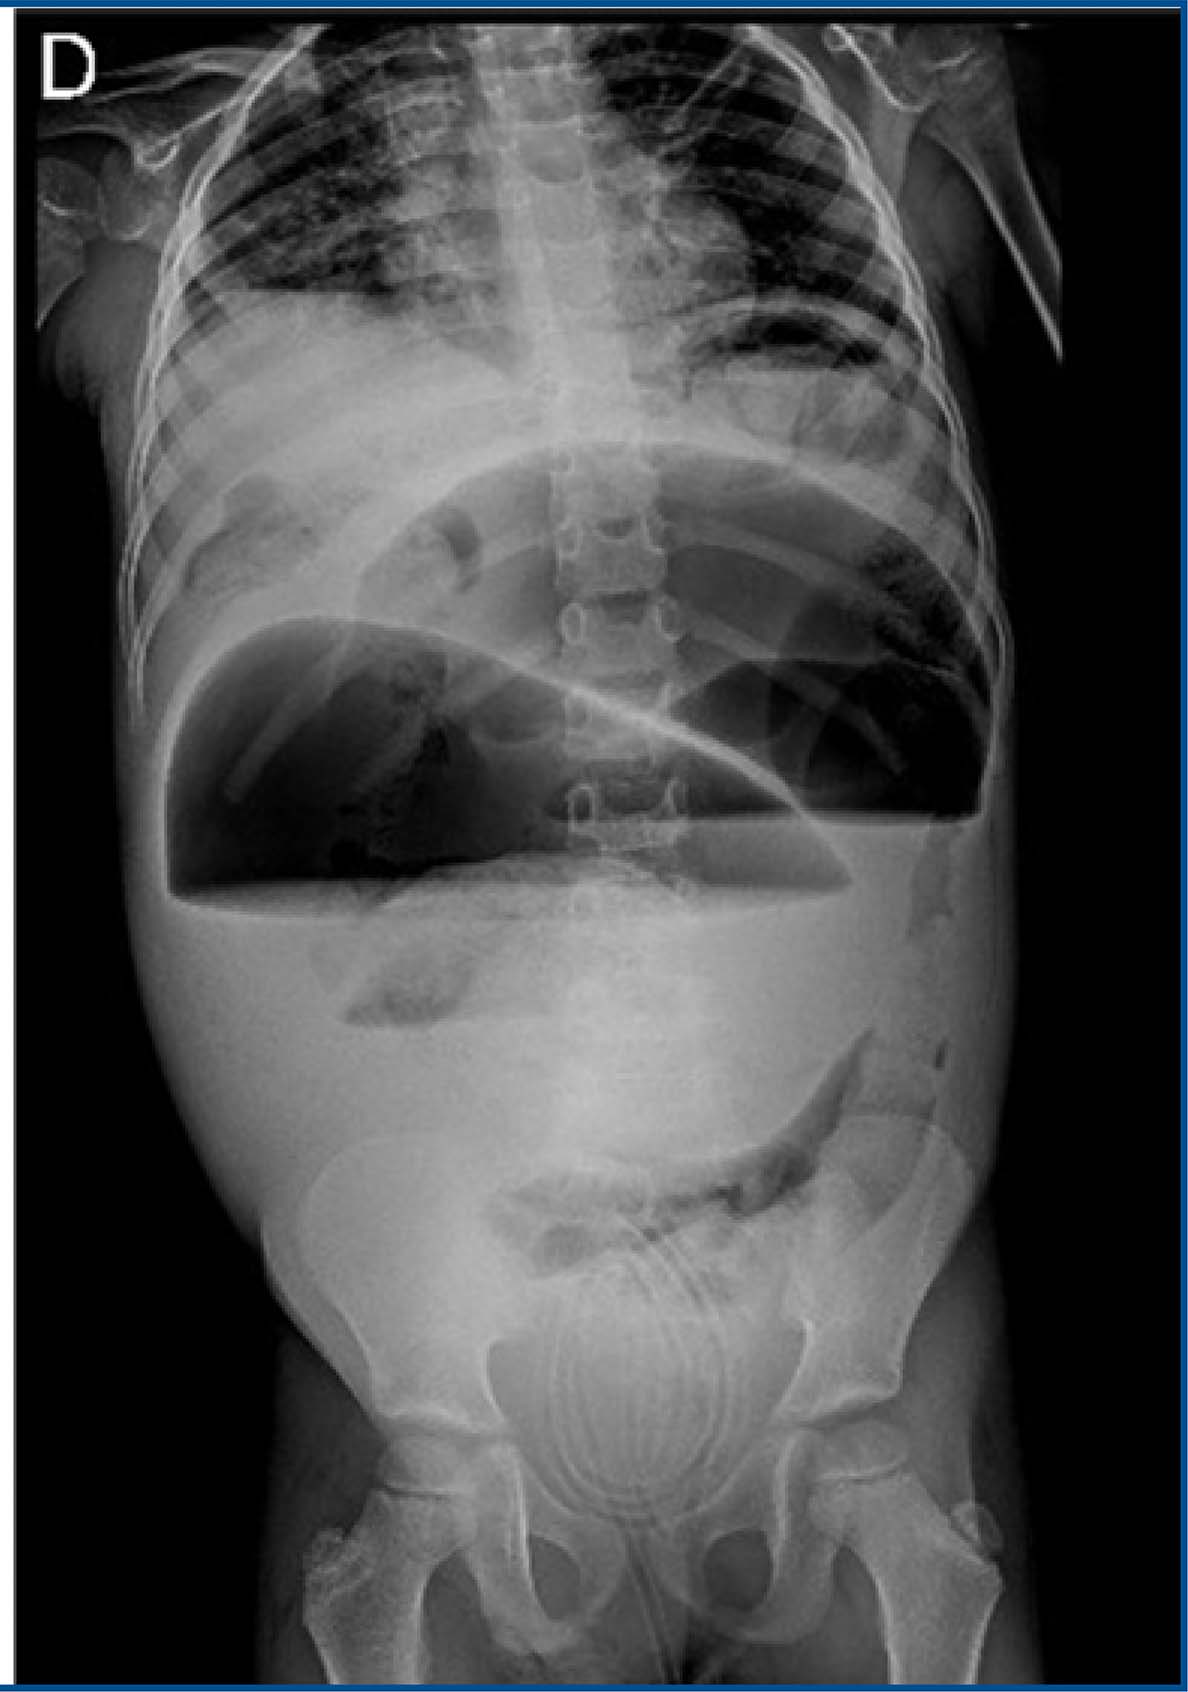

Although hemodynamically stable, the patient continued to report intermittent abdominal pain. On physical examination, the abdomen was tense, with no rebound tenderness. Given these findings, a follow-up upright abdominal X-ray was ordered (figures 2 and 3), as the initial supine bedside X-ray showed no significant abnormalities.

Figure 2 : The plain film suggests the presence of a sigmoid volvulus

Figure 3 : The plain film suggests the presence of a sigmoid volvulus

The follow-up imaging revealed the “coffee bean” sign, leading to a sigmoid volvulus diagnosis. Surgical intervention was deemed necessary, and an exploratory laparotomy was performed. This confirmed the presence of a volvulus with three complete twists, accompanied by necrosis of the entire sigmoid colon, though without perforation (figure 4). The volvulus was successfully untwisted, and the necrotic sigmoid segment was resected. The distal rectal stump was amputated, and a Brooke colostomy was created. The procedure was completed without complications.

The clinical presentation typically includes abdominal pain, distension, and constipation, often associated with colonic transit disturbances, as seen in our case. Radiological imaging, such as the classic “coffee bean” sign observed in abdominal X-rays, is essential for early diagnosis, as demonstrated in this case9,10 This finding aligns with the literature, which suggests that early identification of the sign can reduce the risk of severe complications, such as intestinal perforation9,11.